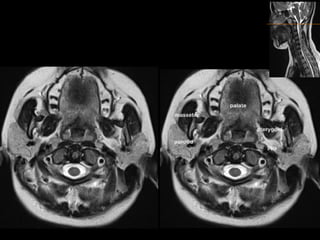

Case 3

• 31 year old male presenting with multiple

cranial nerve palsies on right side.

Nasopharyngeal tumor extending to skull

base and to right cavernous sinus axial fat

suppressed STIR sequence

Post contrast T1 showing entire extent of tumor.

Diagnosis- nasopharyngeal carcinoma

• MRI is ideal to assess extent of tumor , in

particular intracranial/ perineural extension.